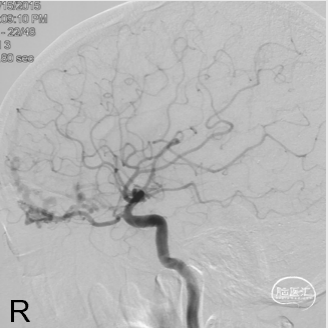

Marathon微导管在Hybrid0.007微导丝导引下经左侧眼动脉超选至左侧筛前动脉,接近瘘口。

通过Marathon微导管超选造影,显示微导管楔入到靠近瘘口的动脉端。

通过Marathon微导管注入Onyx 18,胶向瘘口弥散,并弥散至镰前动脉。

停顿后进一步注射Onyx18,此时胶向对侧筛前动脉弥散,直至闭塞瘘口和引流静脉起始端。

最终造影瘘口完全不显影。

双侧脉络膜染色正常。